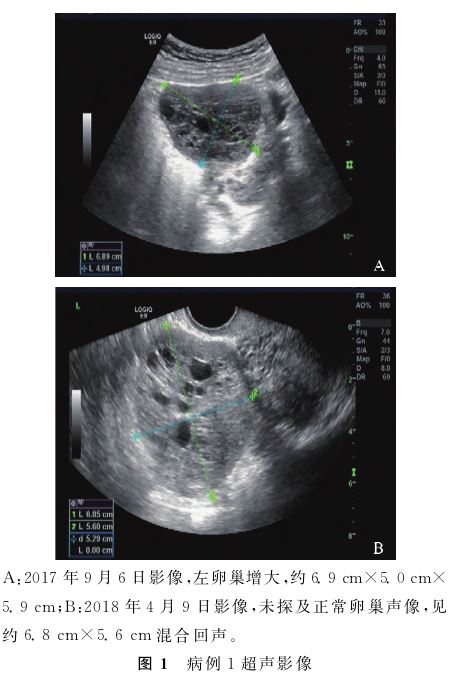

患者14岁月经初潮,月经7d/30~60d。2016年开始无自主月经来潮,服用中药治疗未月经来潮。2017年9月6日于我院门诊就诊,彩超提示左侧卵巢增大6.9cm×5.0cm×5.9cm,内见多个密集无回声(图1A)。性激素六项:卵泡刺激素(FSH)2.54U/L、黄体生成素(LH)20.76U/L、雌二醇

(MPA)后半周期治疗3个月,治疗期间规律撤血。2018年4月24日(撤血第3天)性激素六项:FSH 1.09U/L、LH 20.76U/L、E2183.39pmol/L、T 4.09nmol/L、 P 0.19nmol/L、PRL 0.32nmol/L;复查彩超示左附件区见约6.8cm×5.6cm的混合回声,内见多个无回声,未探及正常卵巢声像(图1B),考虑卵巢肿瘤可能。

本文中病例1的彩超影像类似于Gu等[11] 所报告病例,病例1首次彩超检查提示卵巢增大,诊断为P-COS,治疗后复查时彩超提示卵巢肿瘤。复习前后2次彩超图像(图1),考虑第1次误诊是因为彩超及妇科大夫均对此疾病认识不足有关。